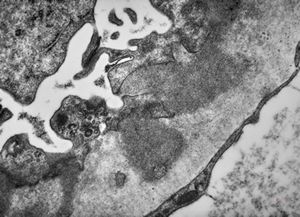

M,22y. | type II membranoproliferative glomerulonephritis